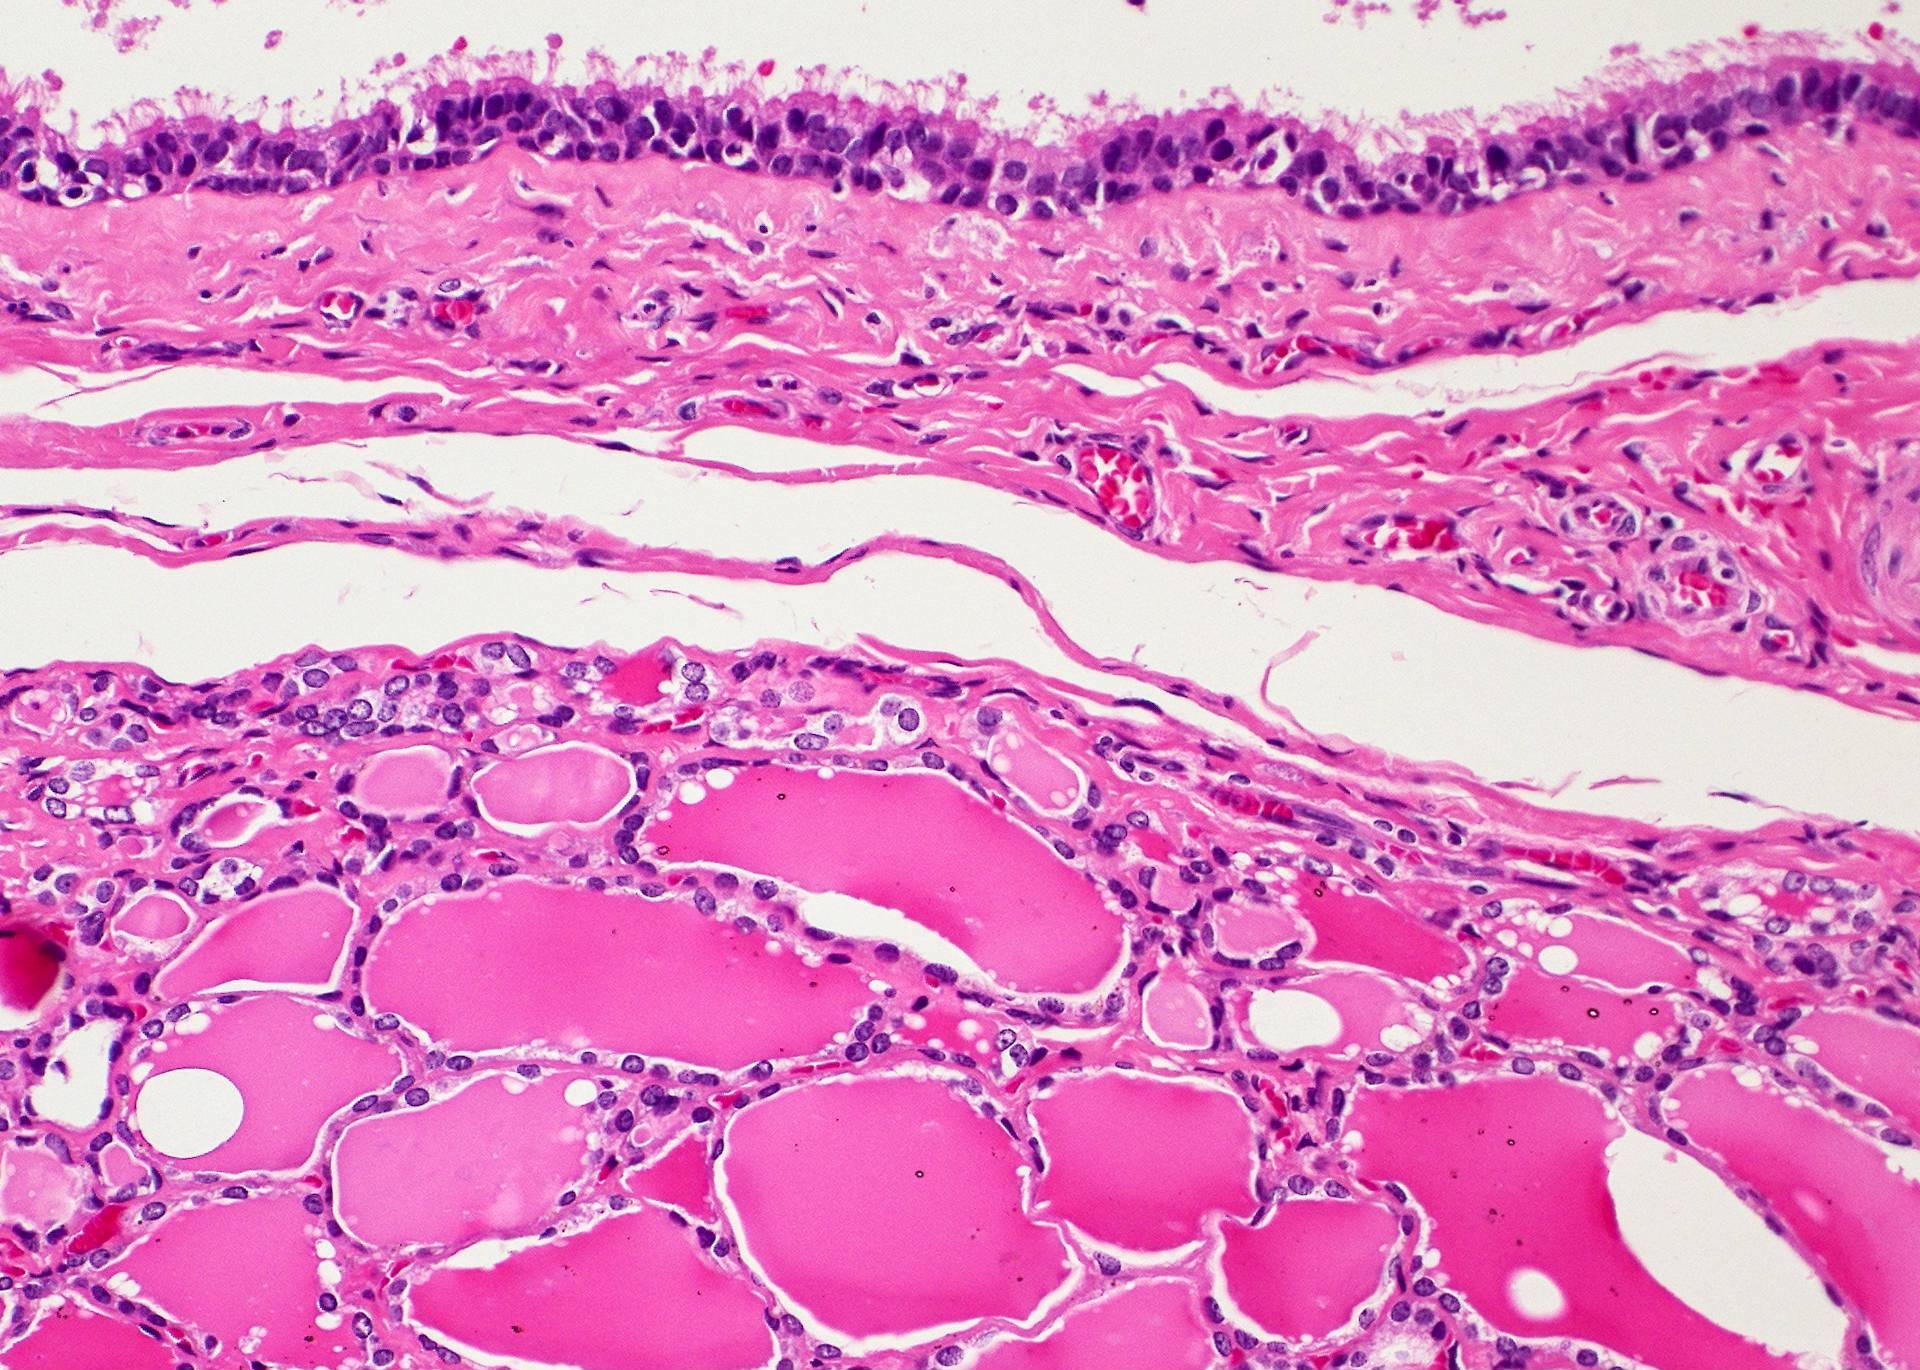

Microscopic (histologic) description

- Type of epithelial lining varies by site, and combinations of the types below can be seen in a single cyst (Head Neck Pathol 2013;7:50):

- Ciliated pseudostratified columnar (respiratory) epithelium in lower neck, perhaps due to its close proximity to upper respiratory tract

- Thyroid follicles in the cyst / duct wall:

- Found in 30% - 60%, with higher yield on serial sections

- More common in infra- versus suprahyoid remnants, on the right paramedian side (Ann Otol Rhinol Laryngol 2000;109:1135)

- Seen in small irregular groups

- Thyroid epithelium may be normal or rarely hyperplastic or neoplastic

- Thyroid tissue often hidden by inflammation (Laryngoscope 2001;111:1002)

- Absence of thyroid tissue does not exclude the diagnosis of TGD cyst

Microscopic (histologic) images

Contributed by Andrey Bychkov, M.D., Ph.D., Mark R. Wick, M.D. and AFIP